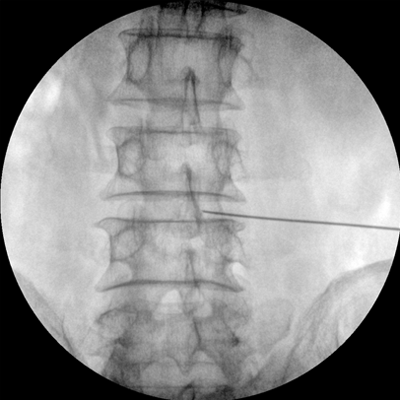

智能化控制系統(tǒng), 讓手術(shù)高效暢捷

四維電動(dòng)運(yùn)動(dòng)控制,平滑定位,使得復(fù)雜角度快速實(shí)現(xiàn)。

專業(yè)的圖像處理系統(tǒng),為您提供高分辨率、高灰階圖像。